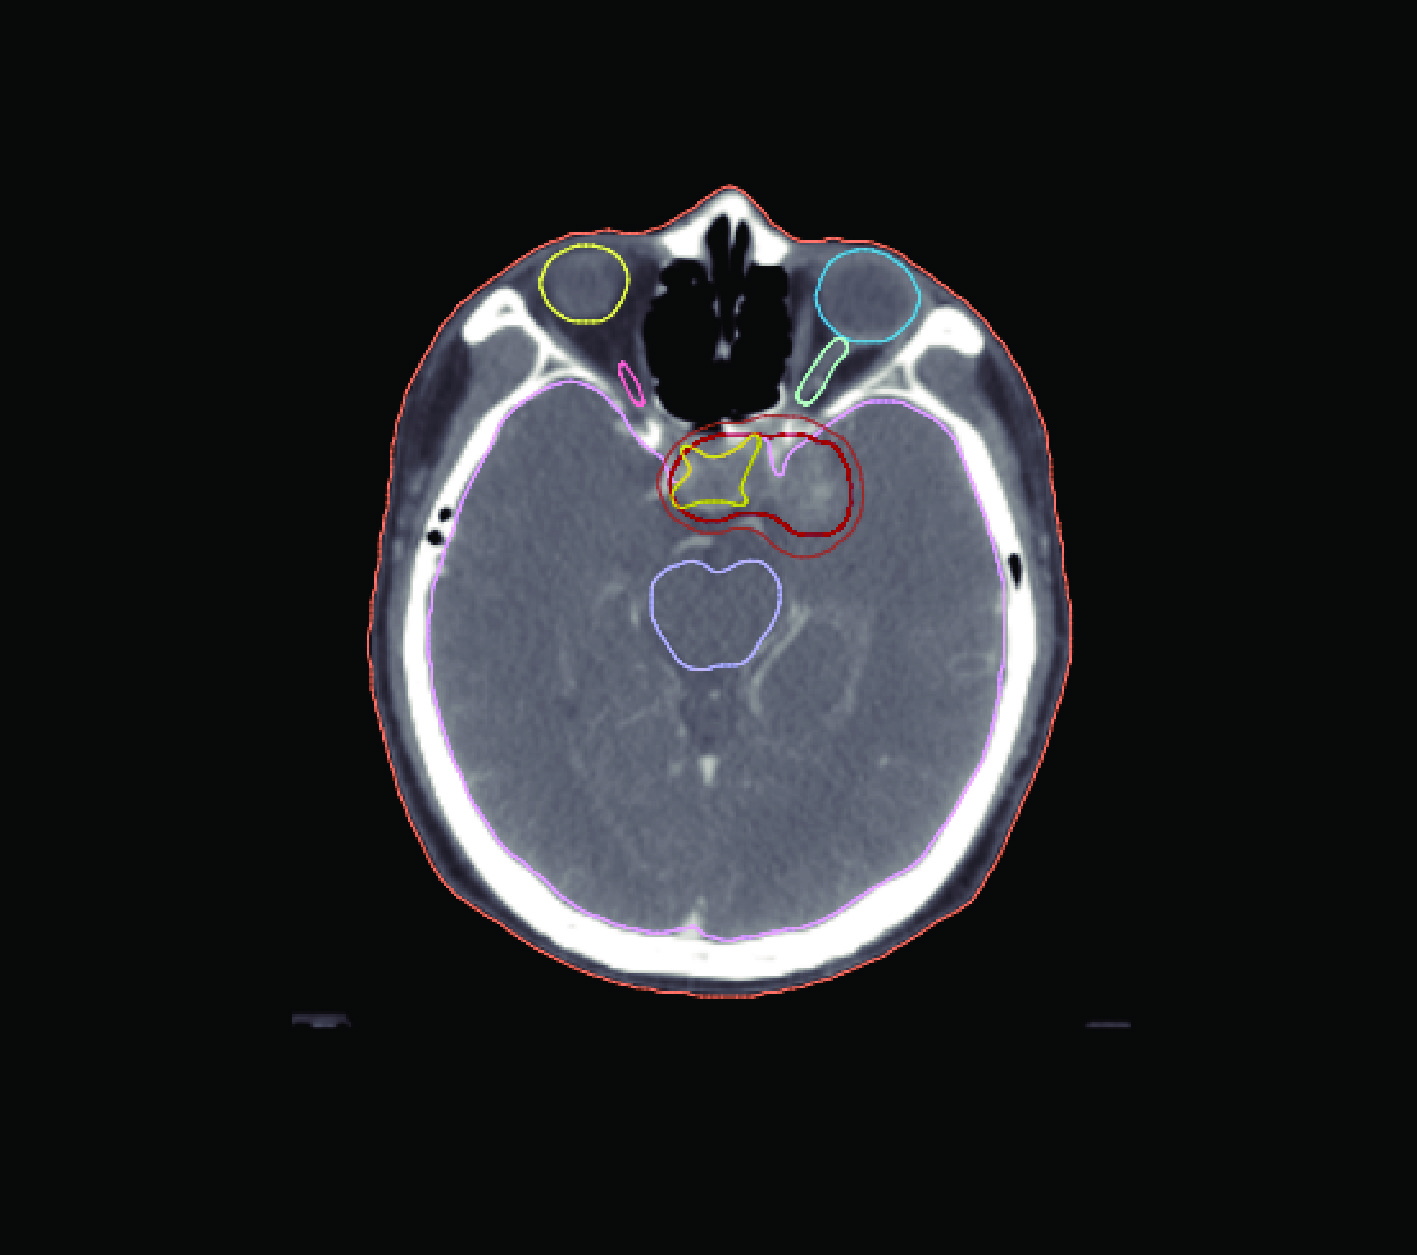

Within the medical-image platform MeVisLab, we complete DICOM registration, target delineation, and RTStruct/RTDose interfaces; the open-source Monte Carlo code OpenMC is used as the engine to execute neutron-transport simulation, realizing HU-to-material mapping and variable-mesh calculation.

Validation with clinical CT data simulated by the system shows that at a depth of 22 cm in the tumour target, the boron dose accounts for 80.9% of the total dose.